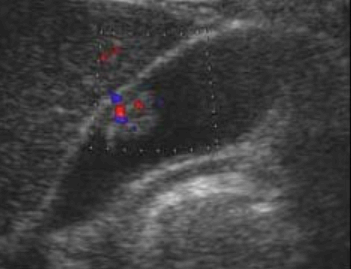

- Color doppler 적용 시 twinkle artifact 가 보인다